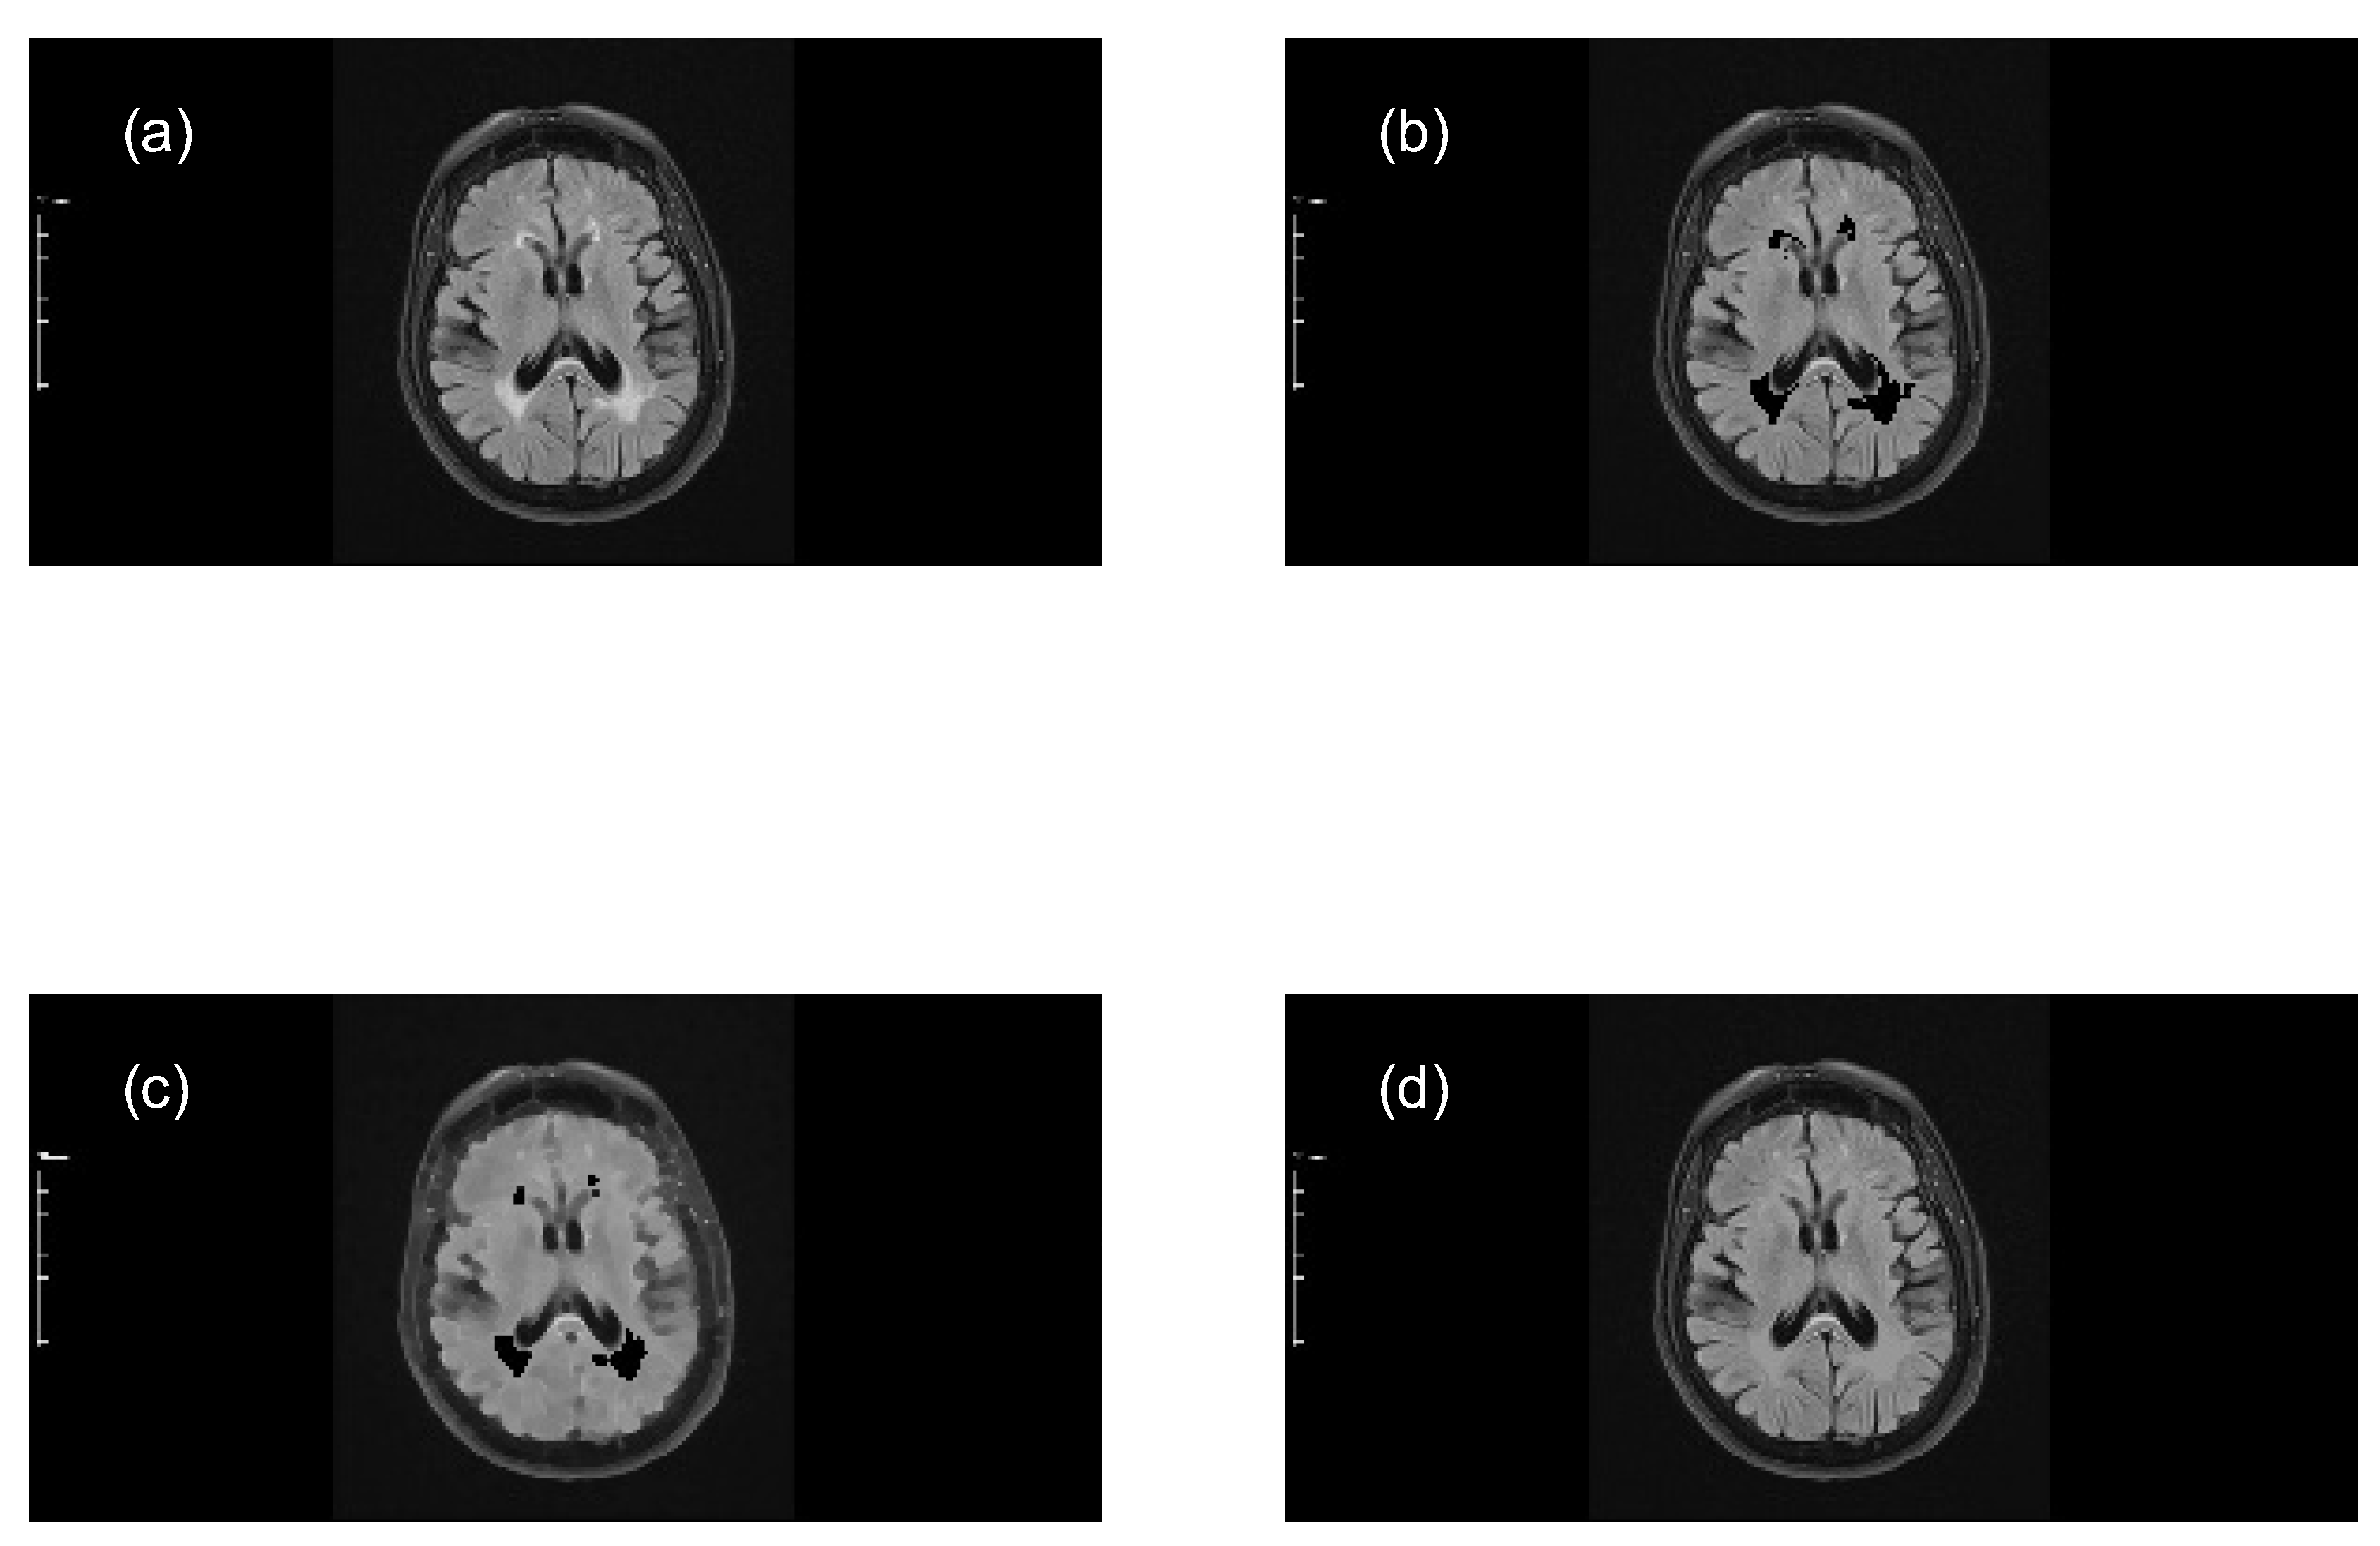

Perform closing morphological transformations on brain images of MS patients (axial and sagittal MRI) to determine the size of the MS lesions, applying the following steps:

- Subtract the lesion areas from the mask image (original image) to acquire a brain image without lesions (with holes).

- Perform a morphological closing transformation on the resulting image (previous step) using a disk-shaped SE with radius r to create a marker image. This operation consists of a dilation followed by erosion using the same SE.

- Perform a closing by reconstruction transformation on the marker image (Equation 6), using the mask image to fill the holes and create a reference image (without lesions), for making comparisons with the mask image (with lesions).

- Compute the granulometry of objects of the mask image and the reference image for different values of radius () of the SE.

- Determine the size of MS lesions by computing the differences in granulometry measurements of the mask image and the reference image to support the decision of specialists in estimating the disease progress.